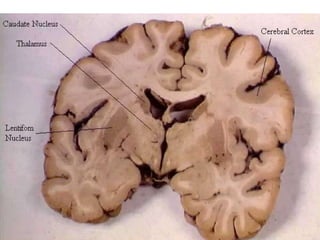

Basal Ganglia This area of grey matter lies deep within the cerebral hemispheres Consist of  the  caudate nucleus ,  putamen  and  globus pallidus .  They are functionally important for  controlling voluntary movements and establishing postures .  It influences skeletal muscle tone When they are altered - say in disorders like Huntington disease or Wilson disease - the person has unwanted movements, such as involuntary jerking movements of an arm or leg or spasmodic movement of facial muscles.

The  caudate   nucleus  and  putamen  along with the interposed anterior limb of the internal capsule are collectively known as the  corpus striatum  (i.e. striated body) because of their appearance.  Similarly, the shape of the  putamen  and  globus   pallidus  resembles a lens, and they are collectively called the  lenticular nucleus .

Basal Ganglia Thisarea of grey matter lies deep within the cerebral hemispheres Consist of the caudate nucleus , putamen and globus pallidus . They are functionally important for controlling voluntary movements and establishing postures . It influences skeletal muscle tone When they are altered - say in disorders like Huntington disease or Wilson disease - the person has unwanted movements, such as involuntary jerking movements of an arm or leg or spasmodic movement of facial muscles.